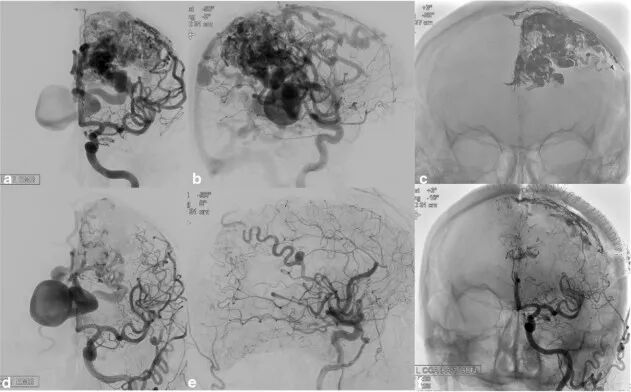

作者认为一期血管内栓塞或者结合显微手术切除是Ⅲ-Ⅴ级AVM患者的合理选择,具有闭塞率高和并发症少的优势。对患者及其家属解释该项技术特点,有利于减轻患者在等待治疗期间的焦虑(图1)。

图1. 1例67岁未破裂左额顶叶Ⅴ级AVM的患者,因广泛的静脉回流表现为进展性右侧偏瘫、失语及吞咽困难。37年前癫痫发作而进行不成功的显微手术切除;最近 6个月前临床病情恶化,计划一期血管内栓塞结合显微手术切除。a、b图示栓塞前DSA显示,累及整个顶叶和额叶后区的畸形团伴向右侧侧脑室突出的扩张静脉瘤。c、d图显示栓塞AVM的Onyx铸形;为避免栓塞后出血,特意保留少量畸形团的前面部分。e、f 图为一期结合显微手术切除后即刻DSA示畸形团完全消除。随访3年,癫痫发作仅1次,未出现新神经功能缺损,语言和吞咽功能有所改善,偏瘫仍然存在。